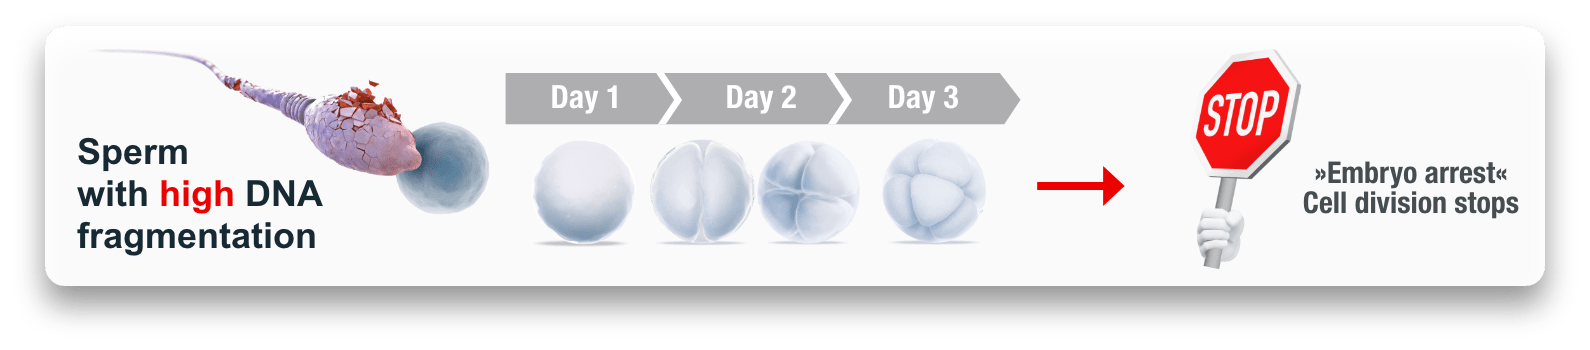

- Significant reduction of DNA fragmentation(Miscarriage) in sperm cells